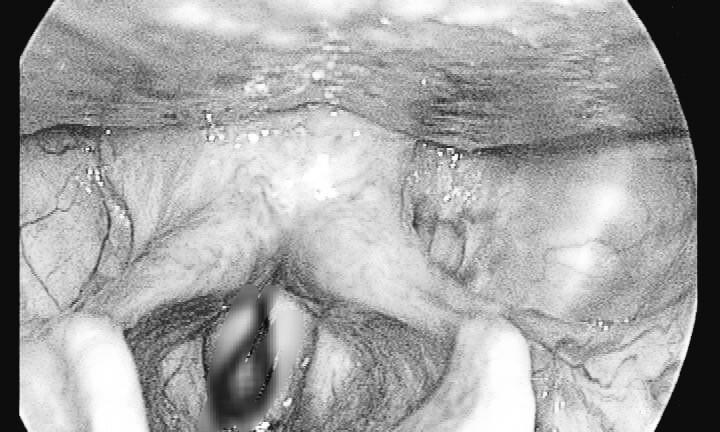

Kết quả siêu âm thấy bìu tụ dịch máu nhiều có nhiều máu cục, mất tính liên tục niệu đạo. Chụp niệu đạo bàng quang ngược dòng có hình ảnh thoát thuốc ra ngoài niệu đạo. Bệnh nhân đc chẩn đoán đứt niệu đạo, chấn thương bìu tinh hoàn 2 bên và phải mổ cấp cứu.

Theo Dân trí, kíp phẫu thuật do BS Bùi Trường Giang, Phó Trưởng Khoa Phụ trách khoa Ngoại tiết niệu, cùng bác sĩ gây mê đã tiến hành phẫu thuật cho bệnh nhân. Đúng như chẩn đoán ban đầu, bệnh nhân sau phẫu tích, phát hiện vùng bìu 2 bên, tinh hoàn 2 bên đụng dập tụ máu nhiều. Kiểm tra niệu đạo thấy đứt dời 2 đầu niệu đạo trước.

Các bác sĩ tiến hành cắt lọc lấy máu tụ vùng bìu 2 bên, khâu bảo tồn tinh hoàn. Đồng thời, tiến hành cắt lọc tổ chức dập nát vùng niệu đạo trước, khâu nối thì niệu đạo thì đầu. Sau phẫu thuật đặt sonde tiểu, kiểm tra tiểu lưu thông tốt, dự kiến khoảng 1 tuần bệnh nhân sẽ ra viện.